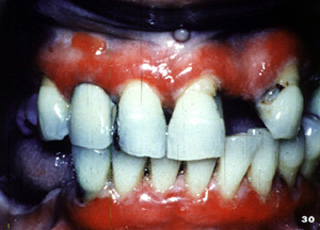

El penfigoide benigno tiene una marcada tendencia a involucrar la encía marginal. La descripción clínica a menudo usada para estas lesiones es "gingivitis descamativa" Debe señalarse que ésta es sólo una descripción clínica y no un diagnóstico definitivo. En la encía  tiene una marcada apariencia eritematosa.

Aquí hay otro paciente con la encía afectada por la enfermedada..